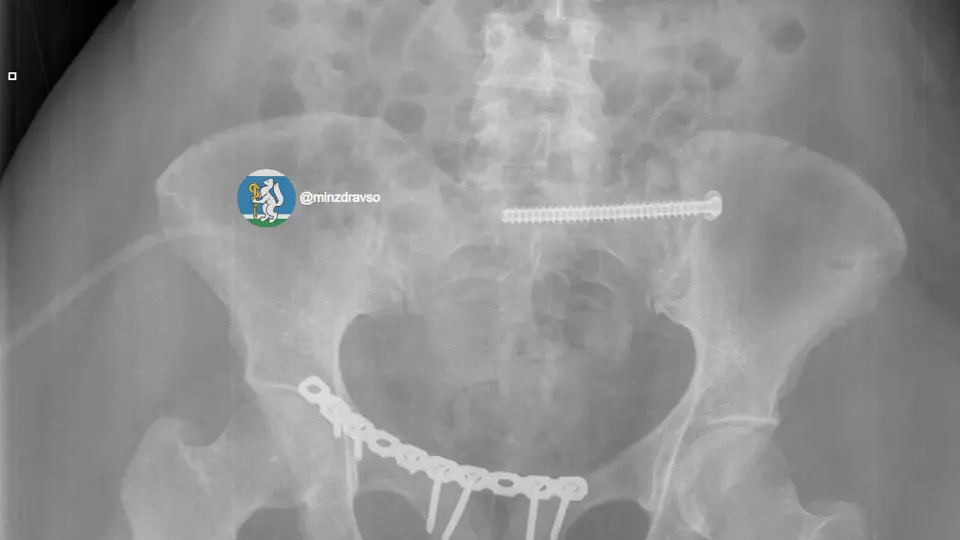

44-летнюю пострадавшую доставили в больницу в состоянии тяжёлого травматического шока — на грани жизни и смерти. Диагноз: закрытая черепно-мозговая травма, ушиб мозга, повреждение челюстно-лицевых костей, рёбер, двусторонний пневмоторакс, оскольчатый перелом ключицы и раздробленные кости таза.

Крайне тяжёлое повреждение таза грозило женщине массивной кровопотерей.

В первые 15 минут провели все необходимые исследования. Врачи скрепили отломки костей всех повреждённых сегментов аппаратами внешней фиксации, чтобы стабилизировать зоны переломов и купировать боль. Ключевую роль сыграл мультидисциплинарный подход: совместная работа анестезиологов-реаниматологов, травматологов-хирургов и нейрохирургов.

Тактика врачей позволила купировать шок и подготовить организм к основному хирургическому этапу. Затем аппараты внешней фиксации таза демонтировали и установили внутренние металлофиксаторы на ключицу и кости таза. Врачи не только спасли пациентку с тяжелейшими повреждениями, но и минимизировали последствия травм, сохранив качество жизни. Через месяц после аварии женщина вернулась домой.